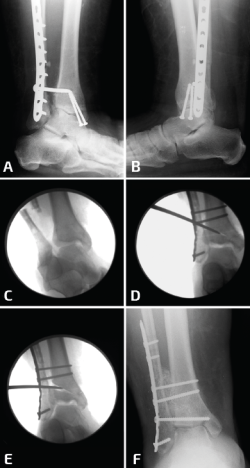

Figura 2. Aquí mostramos la técnica de elongación. Después del desbridamiento de la sindesmosis, se coloca la placa sobre el peroné y de colocan 2 o 3 tornillos distales (A, B). Se coloca un tornillo de 3,5 en el peroné proximal a la placa y el separador de láminas entre el tornillo y el borde proximal de la placa (C, D). En este caso, para corregir la consolidación viciosa del maléolo medial, se realizó una osteotomía (E) y el control de radioscopia intraoperatorio muestra una buena reducción de la sindesmosis (F).

Figura 4. Cuando se realiza la elongación del peroné, este se mueve hacia proximal, evitando la elongación distal. Para evitar esto, se colocan 2 pines proximales a la osteotomía (A). Tras el desbridamiento de la sindesmosis, se elonga el peroné (B) y para mantener la elongación se colocan 2 pines distales a la osteotomía (C) y luego se colocan el injerto y la placa (D).

Una vez más, se desbrida el tejido fibrótico de la cara interna del peroné, pero se deja intacto el ligamento talofibular anterior y el ligamento calcáneo fibular. Para este tipo de osteotomías transversas es importante comprender que, en el proceso de elongación del peroné, al insertar el separador laminar o utilizar el distractor de agujas, se empujará simultáneamente el peroné hacia proximal(10). Por lo tanto, resulta útil insertar 1 o 2 agujas de 1,6 mm en el peroné en la zona proximal a la osteotomía pasando por la tibia para evitar el movimiento del peroné hacia proximal y que solamente se produzca la elongación distal (Figura 4). Una reconstrucción exitosa requiere el posicionamiento anatómico del maléolo externo en la escotadura peronea de la tibia que solo puede detectarse con visualización directa.